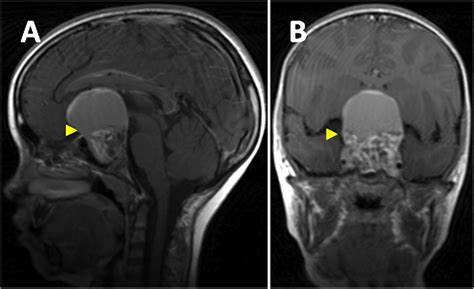

1、关于手术--儿童颅咽管瘤患者多数为牙釉质型,此类颅咽管瘤的特点是:在肿瘤和下丘脑之间缺乏的界面,肿瘤向丘脑指状侵袭,这是造成手术残留、术后复发的重要原因;而且此类肿瘤通常位于是视交叉后方,普遍存在钙化、且瘤体较大,常可导致脑积水(10%-14%)。Di Rocco教授总结了5种手术入路,I型(垂体柄前方型):经蝶、额下、翼点入路;II型(跨垂体柄型):翼点、经蝶、经胼胝体、经终板入路;III型(垂体柄后方型):翼点、经蝶、经胼胝体、经终板入路、幕上幕下联合入路;IV(垂体柄侧方型):翼点、颞下入路;V(异位型):根据肿瘤位置、大小决定手术入路。并展示了精彩的病例和手术视频,内镜、显微镜无一不精,高超的手术技艺令人钦佩。

Di Rocco教授强调:关于视交叉减压,可以通过控制脑积水或者囊液抽吸的办法降低颅内压,囊液抽吸可以选择内镜或者立体定向技术;不要试图分离肿瘤和下丘脑,需要尽可能保护下丘脑;尽量保留垂体柄。但Di Rocco教授统计的一组数据则反映出颅咽管瘤手术现状不容乐观:根治性手术切除率50%-75%,手术相关发病率仍然很高,其中围手术期发病率3%,并发症发生率8.3%-33%,术后激素水平异常80%-全切,视力、神经功能缺陷30%,复发率高达25%。从不良预后看,颅咽管瘤与恶性肿瘤相当。